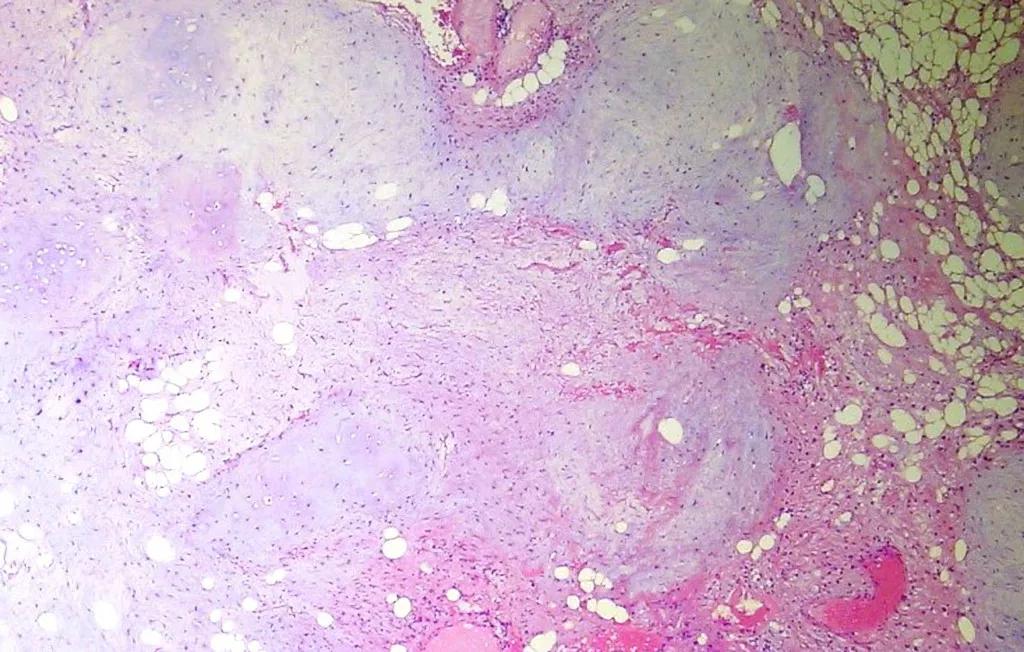

病理大体标本

镜下组织细胞

20x H&E: 病变是实性的,与周围的实质清晰地划定。

在低功率下,可以欣赏到软骨和脂肪组织的混合物。